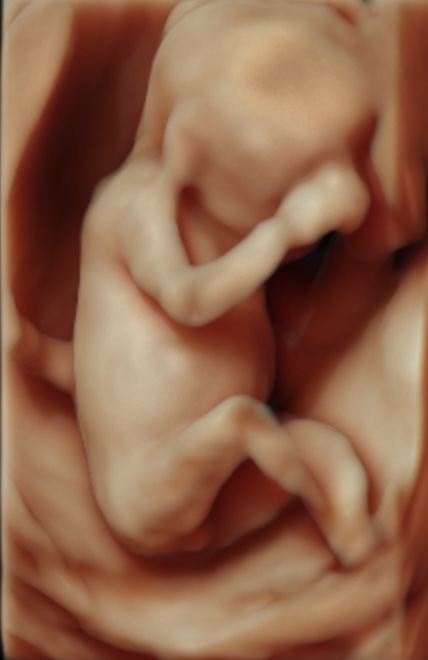

Somos expertos en detección temprana de anomalías. Brindamos una gama completa de Ultrasonidos Fetales y Ecografías 5D-7D: